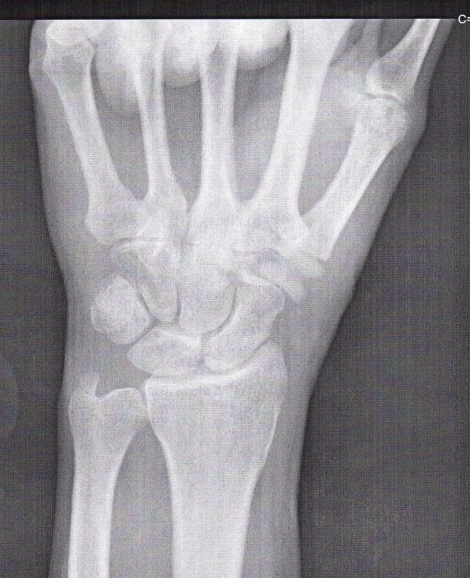

There's a cube-shaped bone at the base of the thumb called the trapezium. I had developed arthritis in the joint between the trapezium and the first bone of the thumb, which means the cartilage on the facing surfaces of those bones had worn away.

You can see the arthritis in this x-ray because there is no space between those two bones (red arrow). The cartilage that separates two bones will show up as a space between the bones in an x-ray because it isn't as dense as bone. As you can see, there's no space here. There was bone-on-bone contact. The surgery was on June 6th, 2014. |